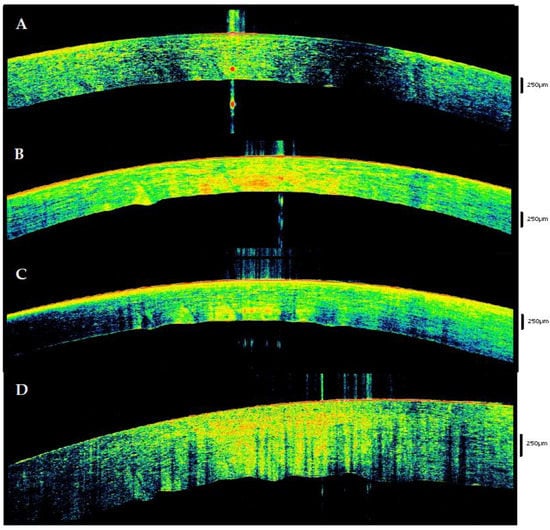

| 3–6 | Lacrimal tear disappears. Binary sign with hyperreflectivity of the outer and inner layer and hyperreflectivity in the middle. | Posterior waves (Nioi Napoli sign grade 0). Thickening of the stroma with initial differentiation between posterior and anterior tissue. In 69,5%, the posterior stroma assumes a wavy morphology. | Hyperreflective respect to the posterior stroma. Presence of Endothelial spots | V-shapes in 56.5% of cases. Nioi–Napoli I (21.7%) |

| 6–9 | Appears like a single, hyperreflective layer in 50% of cases. In 50% ‘binary morphology’. | Differentiation between anterior hyperreflective and posterior hypo-reflective stroma in 56.5% of cases. Presence of one tissue peak that protrudes in the anterior chamber (Nioi-Napoli 1) | Hyper-reflectivity with the presence of multiple spots. | Nioi–Napoli II (21.7%). Initial loosing of the spheric form of the tissue.in 34.7% of cases |

| 9–12 | Single hyperreflective layer in 91.3% of cases. In the 8.7% initial flaking of the epithelium. | Thickening of the stoma. Anterior-posterior differentiation in 100% of cases. Waving with one of two protruding peaks in 14 cases (60.8%). | Unchanged | Nioi–Napoli III (60.8%) |

| 12–17 | Single hyperreflective layer in 100%. Epithelium flacking in 34.7% of cases. | Important thickening, structural inhomogeneity with anterior-posterior differentiation and multiple hyporeflective spots. Posterior waving with more than two peaks in 100% of cases. | Hyperreflective. | Nioi–Napoli IV in 100% of cases. Stromal Striae in 60.8% of cases. |